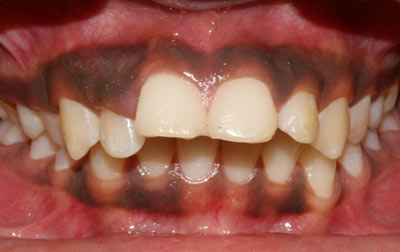

Dental laminates closely resemble dental veneers and are becoming a preferred choice for enhancing smiles. Available in composite or porcelain, these thin, customized shells offer numerous advantages. They effectively mask stains and discolorations on individual teeth, especially when conventional teeth-whitening methods fall short. In cases of stubborn and deep dental stains caused by factors like excessive fluoride or certain medications, standard whitening procedures often prove ineffective. Dental laminates step in as a promising solution, especially with lighter-colored variants effectively concealing teeth with severe discoloration.

Beyond staining, laminates address unexpected dental issues such as chips, wear, or breakage. They swiftly camouflage imperfections, whether on a single tooth or multiple ones, revitalizing the overall dental aesthetic. Dental laminates also serve as a corrective measure for uneven, misaligned teeth, as well as indentations and protrusions. A minor enamel trim enhances the adherence of these thin shells while preventing overcrowding and closing gaps between teeth. With the ability to seamlessly match natural tooth shades, dental laminates seamlessly integrate into the oral environment. Patients even have the flexibility to select their desired level of tooth whiteness.

Notably, the effects of dental laminates are enduring, eliminating the need for subsequent adjustments or reshaping. In essence, dental laminates offer a versatile and lasting solution for an array of dental imperfections, yielding confident smiles without the constraints of staining, damage, or misalignment.

Smile makeover:

Radiating confidence through a beaming smile can truly uplift your spirits. A captivating smile holds significant sway in social and professional spheres, enhancing your overall appeal. However, numerous individuals refrain from revealing their teeth in public or photographs due to personal dissatisfaction. If you find yourself in this category, why not consider allowing us to assist you in attaining the smile you've always envisioned? Embark on a journey toward your ideal smile with our transformative smile makeover. A smile makeover transcends the mere resolution of dental issues as they arise. It constitutes a holistic plan to rejuvenate your smile, intricately tailored to complement your distinct facial features and aesthetic inclinations. The outcomes are nothing short of remarkable—both in terms of your visual transformation and the surge of newfound confidence you'll experience.